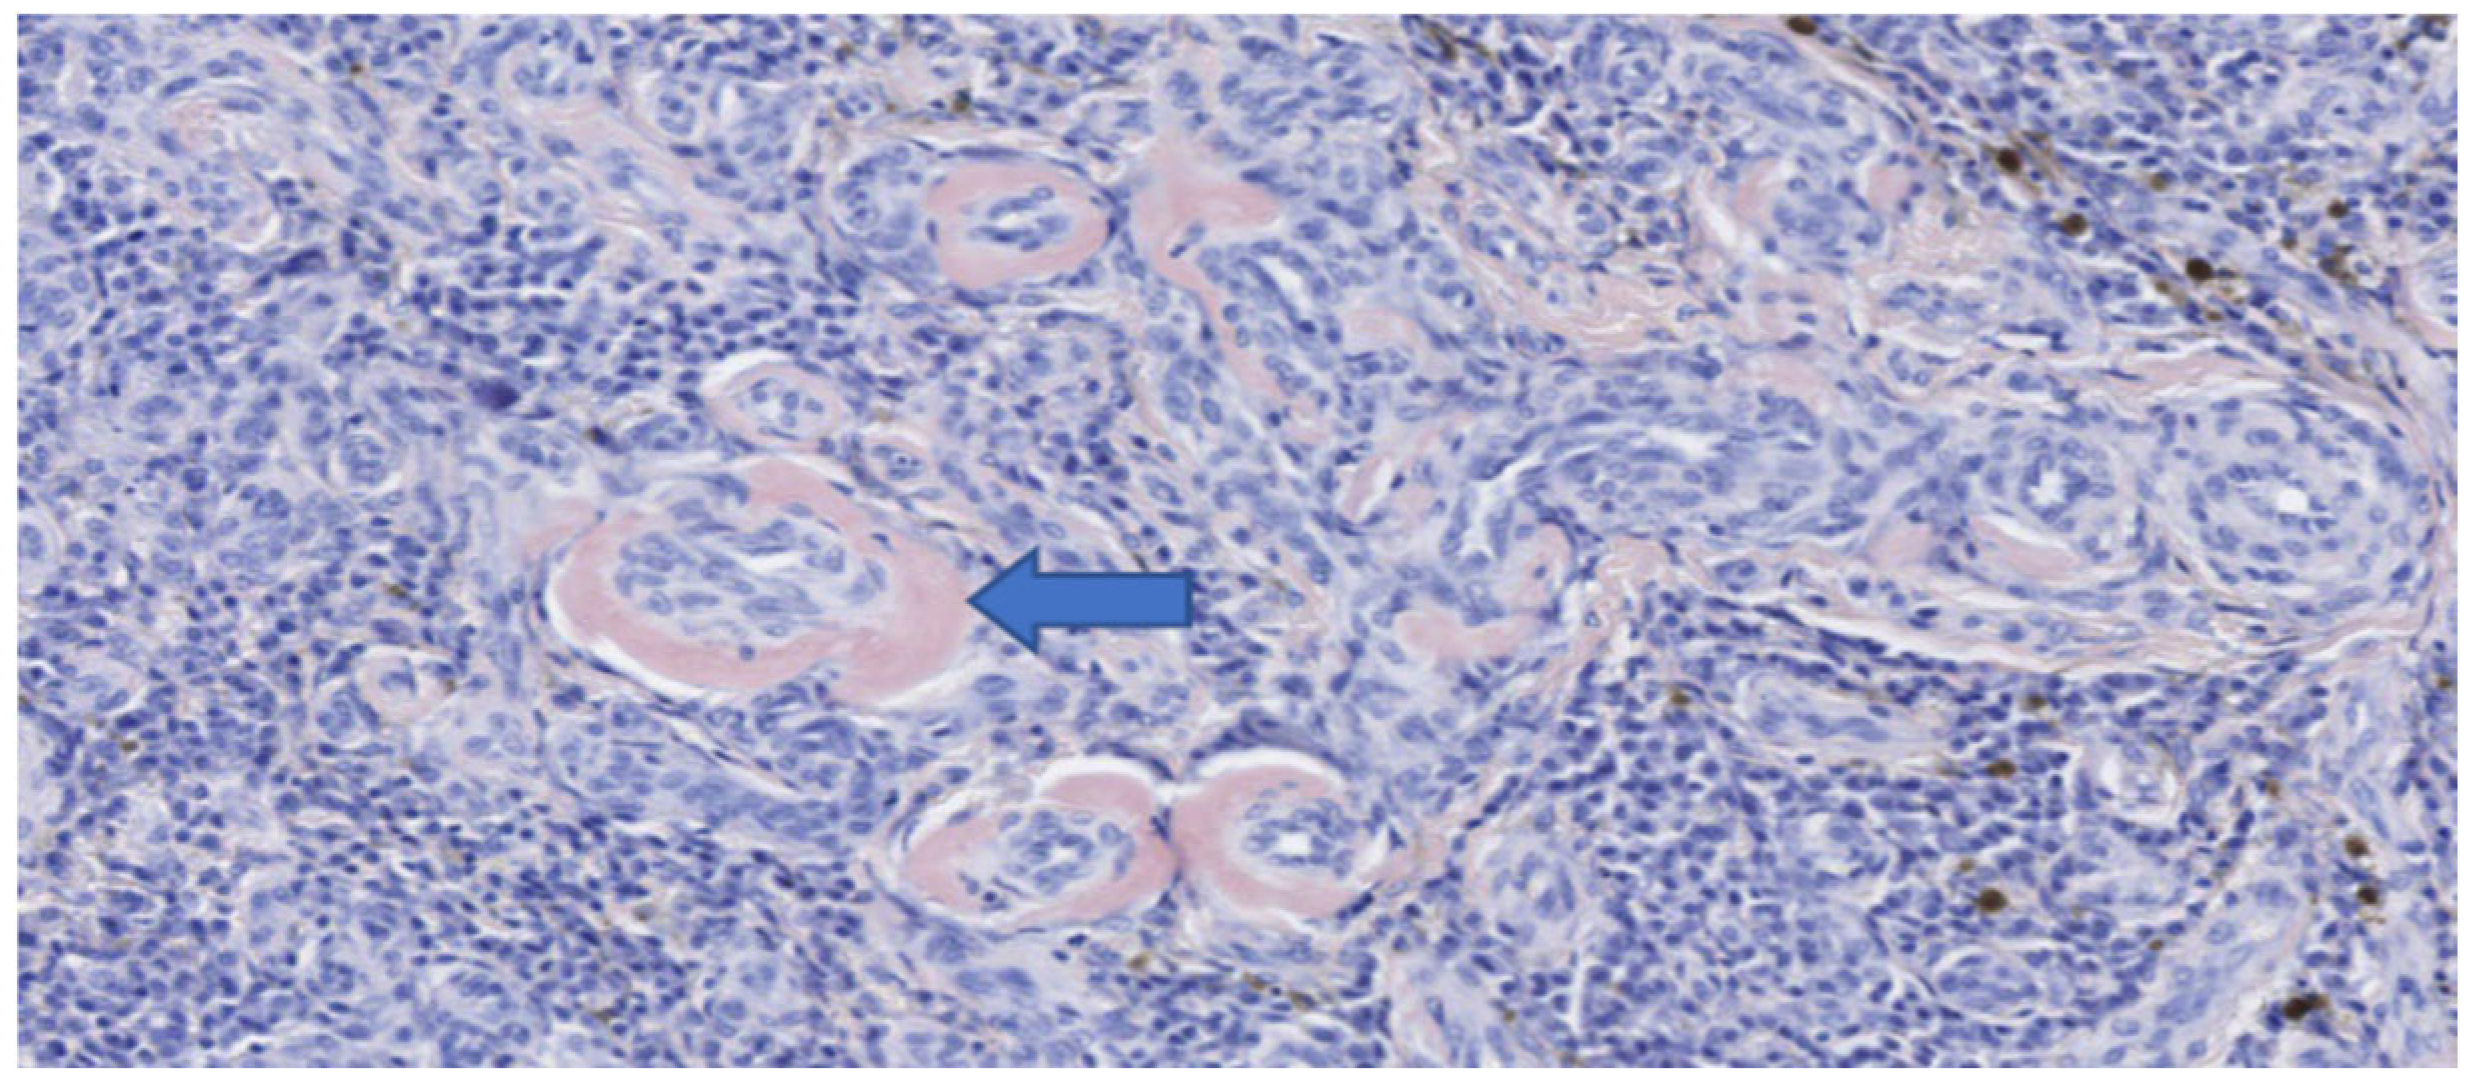

Figure 7.

Histopathology of the esophageal mass after surgical excision (hematoxylin and eosin stain). (A) Background of round cells with aggregates of extracellular amorphous material, presumptive amyloid. (B) Higher power view of neoplastic round cells, amidst hemosiderin.

The mass measured approximately 7 cm in length (Figure 6). Histopathological and immunohistochemical examination of the mass revealed that despite the abundant necrosis and hemorrhage, there was a neoplastic proliferation of plasma cells with extracellular amorphous eosinophilic material interpreted as amyloid based on Congo red staining (Figure 7 and Figure 8). Therefore, a diagnosis of a plasma cell tumor with perivascular amyloid deposition was made. This diagnosis was confirmed by immunohistochemistry (IHC) with a monoclonal anti-multiple myeloma oncogene 1 (MUM-1) antibody (clone MUM1p, Catalog #GA64461-2, Dako Omnis, Agilent, Richmond, VI, USA) (Figure 9).